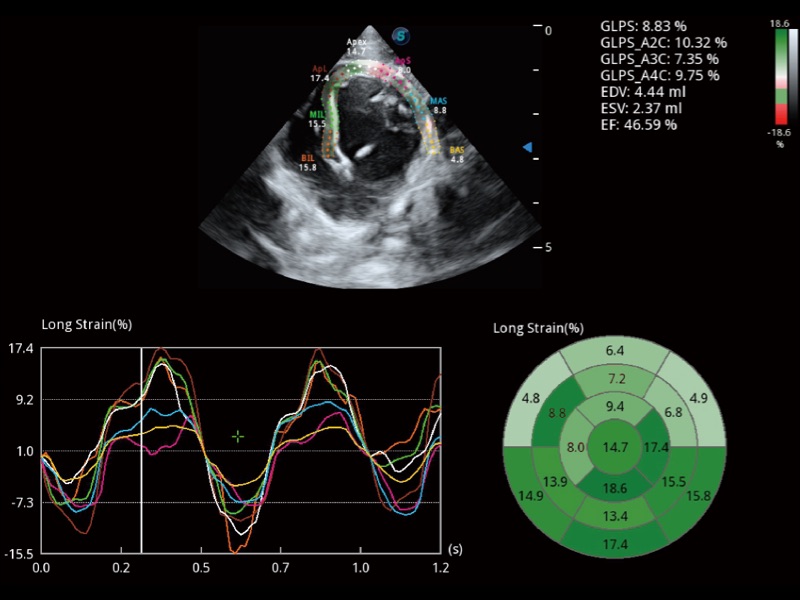

能夠基于左心室壁追蹤和辛普森法,自動(dòng)計(jì)算射血分?jǐn)?shù),支持多個(gè)可移動(dòng)點(diǎn)描跡,與手動(dòng)測(cè)量相比,極大節(jié)省了動(dòng)物醫(yī)生的時(shí)間和精力。

具備多種協(xié)議可選,同時(shí)支持17階段劃分法和專(zhuān)業(yè)的SE報(bào)告。

通過(guò)360度任意調(diào)節(jié)3條M型取樣線(xiàn),在同一心動(dòng)周期上觀(guān)察心臟不同位置的運(yùn)動(dòng)曲線(xiàn),得到準(zhǔn)確的心功能測(cè)量數(shù)據(jù),有效評(píng)估心肌運(yùn)動(dòng)及左心室功能。

實(shí)時(shí)用顏色表示心肌組織運(yùn)動(dòng),觀(guān)察和定量組織的運(yùn)動(dòng)情況,對(duì)快速檢測(cè)與評(píng)估心肌的灌注和活性、電傳導(dǎo)及心肌收縮和舒張功能等均能提供重要的診斷信息。

當(dāng)心臟測(cè)量結(jié)果超出正常范圍時(shí),可實(shí)時(shí)預(yù)警提示動(dòng)物醫(yī)生,減少疾病漏診概率。